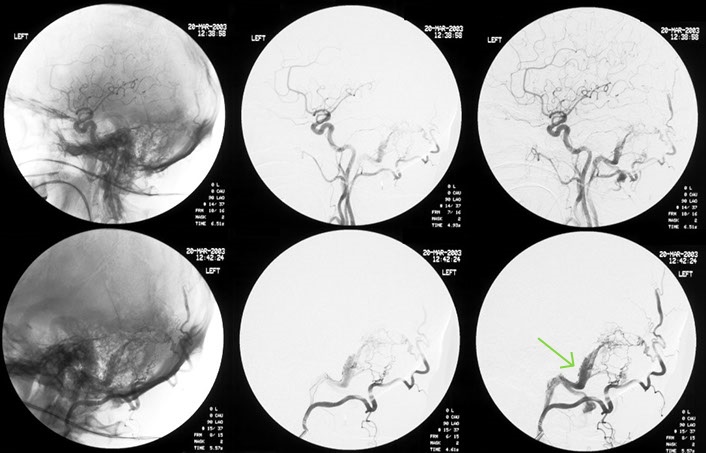

This patient had a large cerebral haemorrhage, from an arteriovenous malformation fed by branches of the internal carotid and vertebral arteries.

Selective catherization of feeding vessels revealed a small aneurysm which presumably is the cause of the haemorrhage, as indicated by the green arrow.

The aneurysm was occluded by a minute amount of glue, which can be seen on the bottom left of the image.